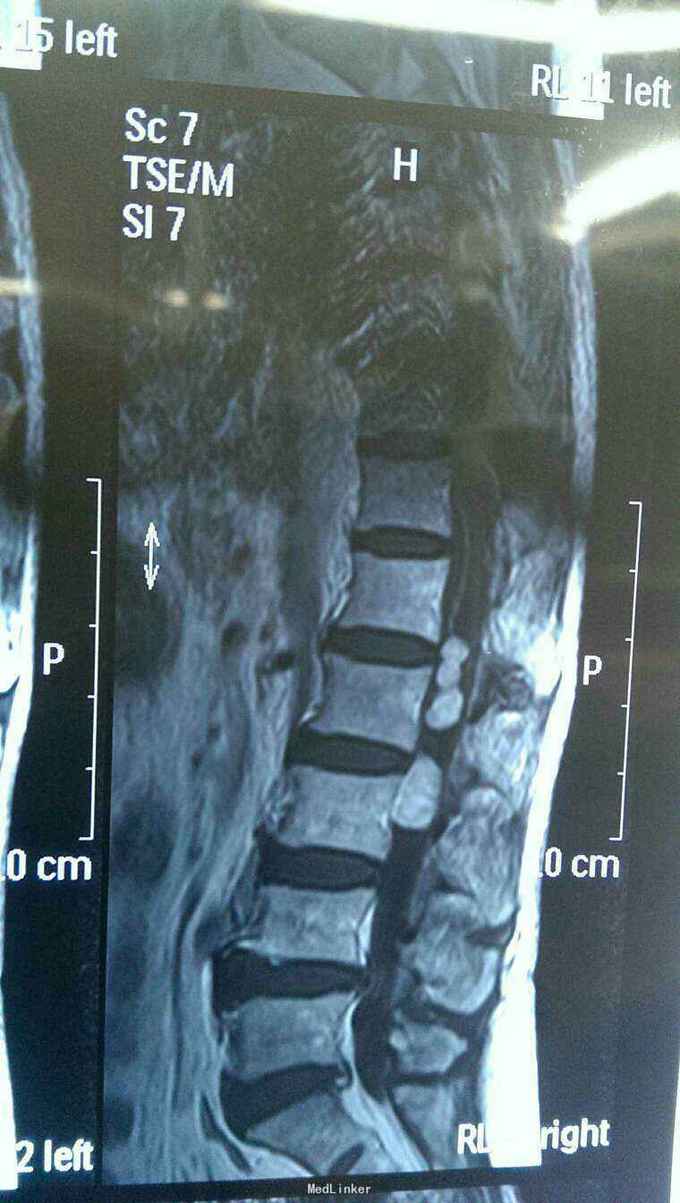

患者以腰部疼痛一年伴右侧大腿麻木两个月为主诉入院。患者入院一年前出现腰部疼痛,当时未注意。两个月前患者自诉右侧大腿麻木,运动尚可,无尿便障碍。门诊行核磁共振检查后以椎管内占位病变收入院。既往健康。

神志清楚,语言流利。颅神经检查未见异常。右侧臀部一下浅深感觉减退,肌力四级。生理反射存在,病理反射未引出。括约肌功能正常。核磁共振提示腰1--3椎管内多发病变,明显强化。

入院诊断椎管内多发占位病变,神经纤维瘤。完善术前准备后行后正中入路神经纤维瘤切除术。术中见马尾神经生长多个肿瘤,与其余神经无粘连,完整切除肿瘤。